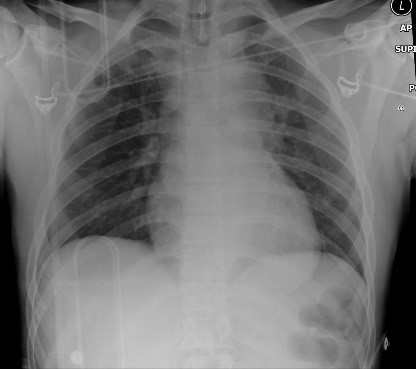

Given the patient’s abrupt change in mental status and apnea, you decide to call a trauma alert before he reaches the emergency department. While the trauma team is being mobilized, he arrives. On initial examination, you see an adult male in a cervical collar without spontaneous respirations being supported by bag valve mask ventilation. Blood pressure and heart rate are normal. You decide to intubate given his lack of spontaneous respirations. While maintaining strict in line cervical spine stabilization, the patient is intubated with video laryngoscopy. Endotracheal tube placement is confirmed by direct visualization of the tube passing through the cords and by chest x-ray. He is being placed on a ventilator when the trauma team arrives.

Rapid acceleration/deceleration in restrained occupants of MVCs increases the risk for traumatic aortic catastrophe including transection, rupture and dissection. Perform a thorough vascular examination for pulse deficits and look for mediastinal widening or opacities on chest x-ray. The mediastinum may appear falsely widened and the heart magnified on the portable AP view in normal patients.

All hemothoraces should be considered for drainage, especially in patients with inadequate oxygenation/ventilation. Persistent opacities on chest x-ray can be evaluated in delayed fashion by CT to determine whether significant undrained fluid exists. Indications for emergency thoracotomy include immediate drainage of more than 1000 cc of blood immediately after tube thoracostomy, drainage of 1500 cc from a chest tube in any 24 hour period, continued bleeding from the chest (150-250 cc/hr for 2-4 hours) or repeated need for blood transfusion to maintain hemodynamic stability [10, 14].